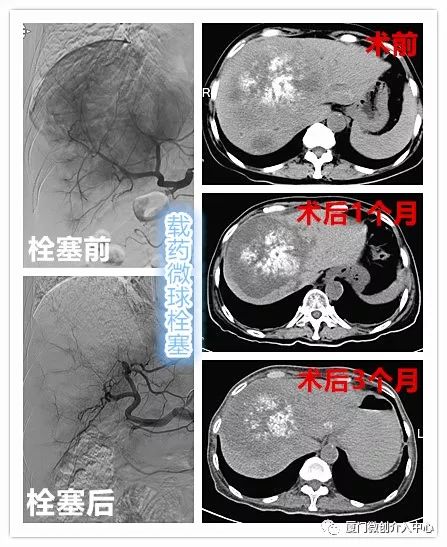

病例2

老年女性患者,诊断为乙状结肠腺癌并肝多发转移。肝脏肿瘤病灶巨大且多发,针对肝脏转移瘤行载药微球栓塞治疗,肠道肿瘤行动脉化疗灌注治疗。

肝动脉化疗栓塞+肠系膜上动脉化疗灌注治疗

术后1月复查提示肝转移瘤病灶内部明显坏死,肿瘤缩小

肠道肿瘤标志物明显下降(CEA 术前:3493 ng/mL,术后:196.3 ng/mL;CA19-9 术前:895.8 U/mL,术后:110.1 U/mL),病灶控制理想。